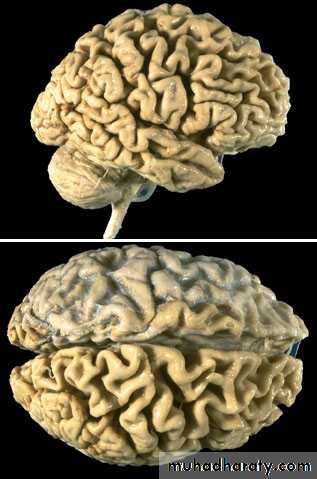

CEREBRAL FORM OF ATHEROSCLEROSIS

Acute form may be as Hemorrhage within

The brain due to rupture

Of atherosclerotic aneurism

Chronic form may be as encephalopathy

With cerebral atrophy (decreasing memory)